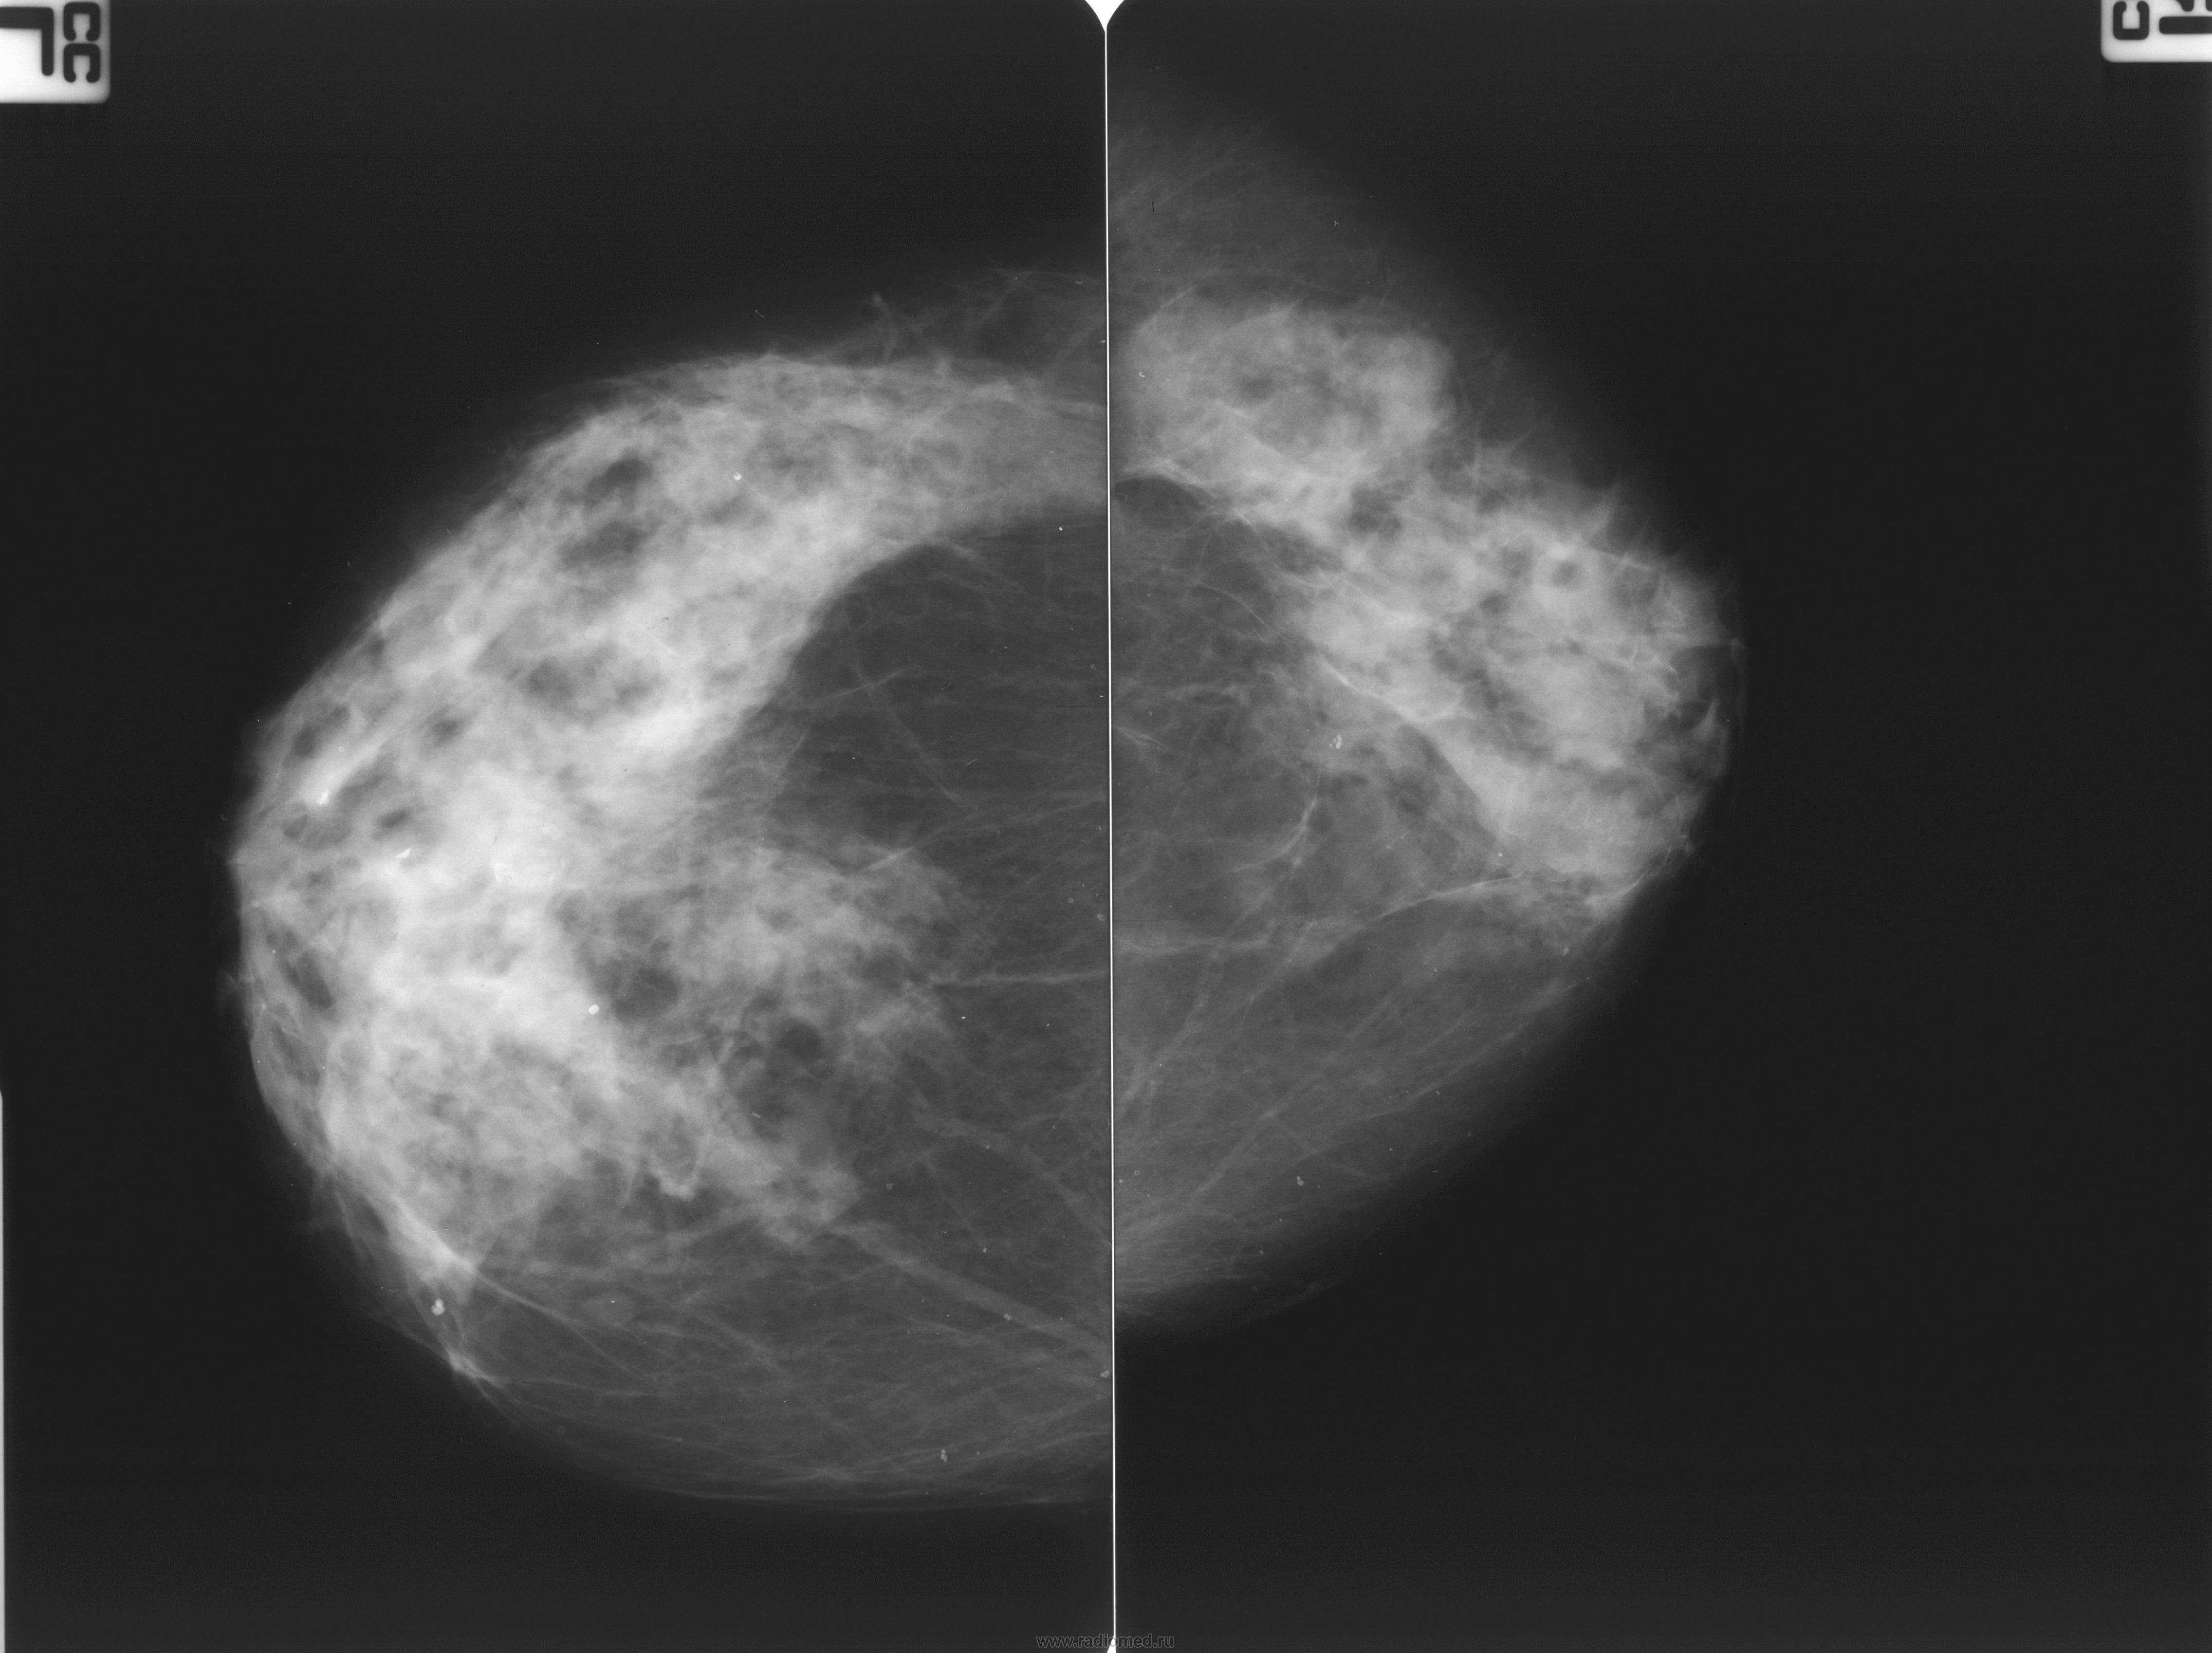

Фиброзно-кистозная мастопатия рентген молочных желез

Фиброзно кистозная мастопатия маммограмма